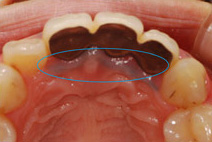

歯を引っ張り上げる時は、矯正治療と同じ要領でワイヤーを使用して少しずつ引っ張り出します。治療中の痛みはほとんどありません。

残った歯を歯茎の上まで引っ張り上げ、被せ物の土台にすることで抜歯を回避するのです。